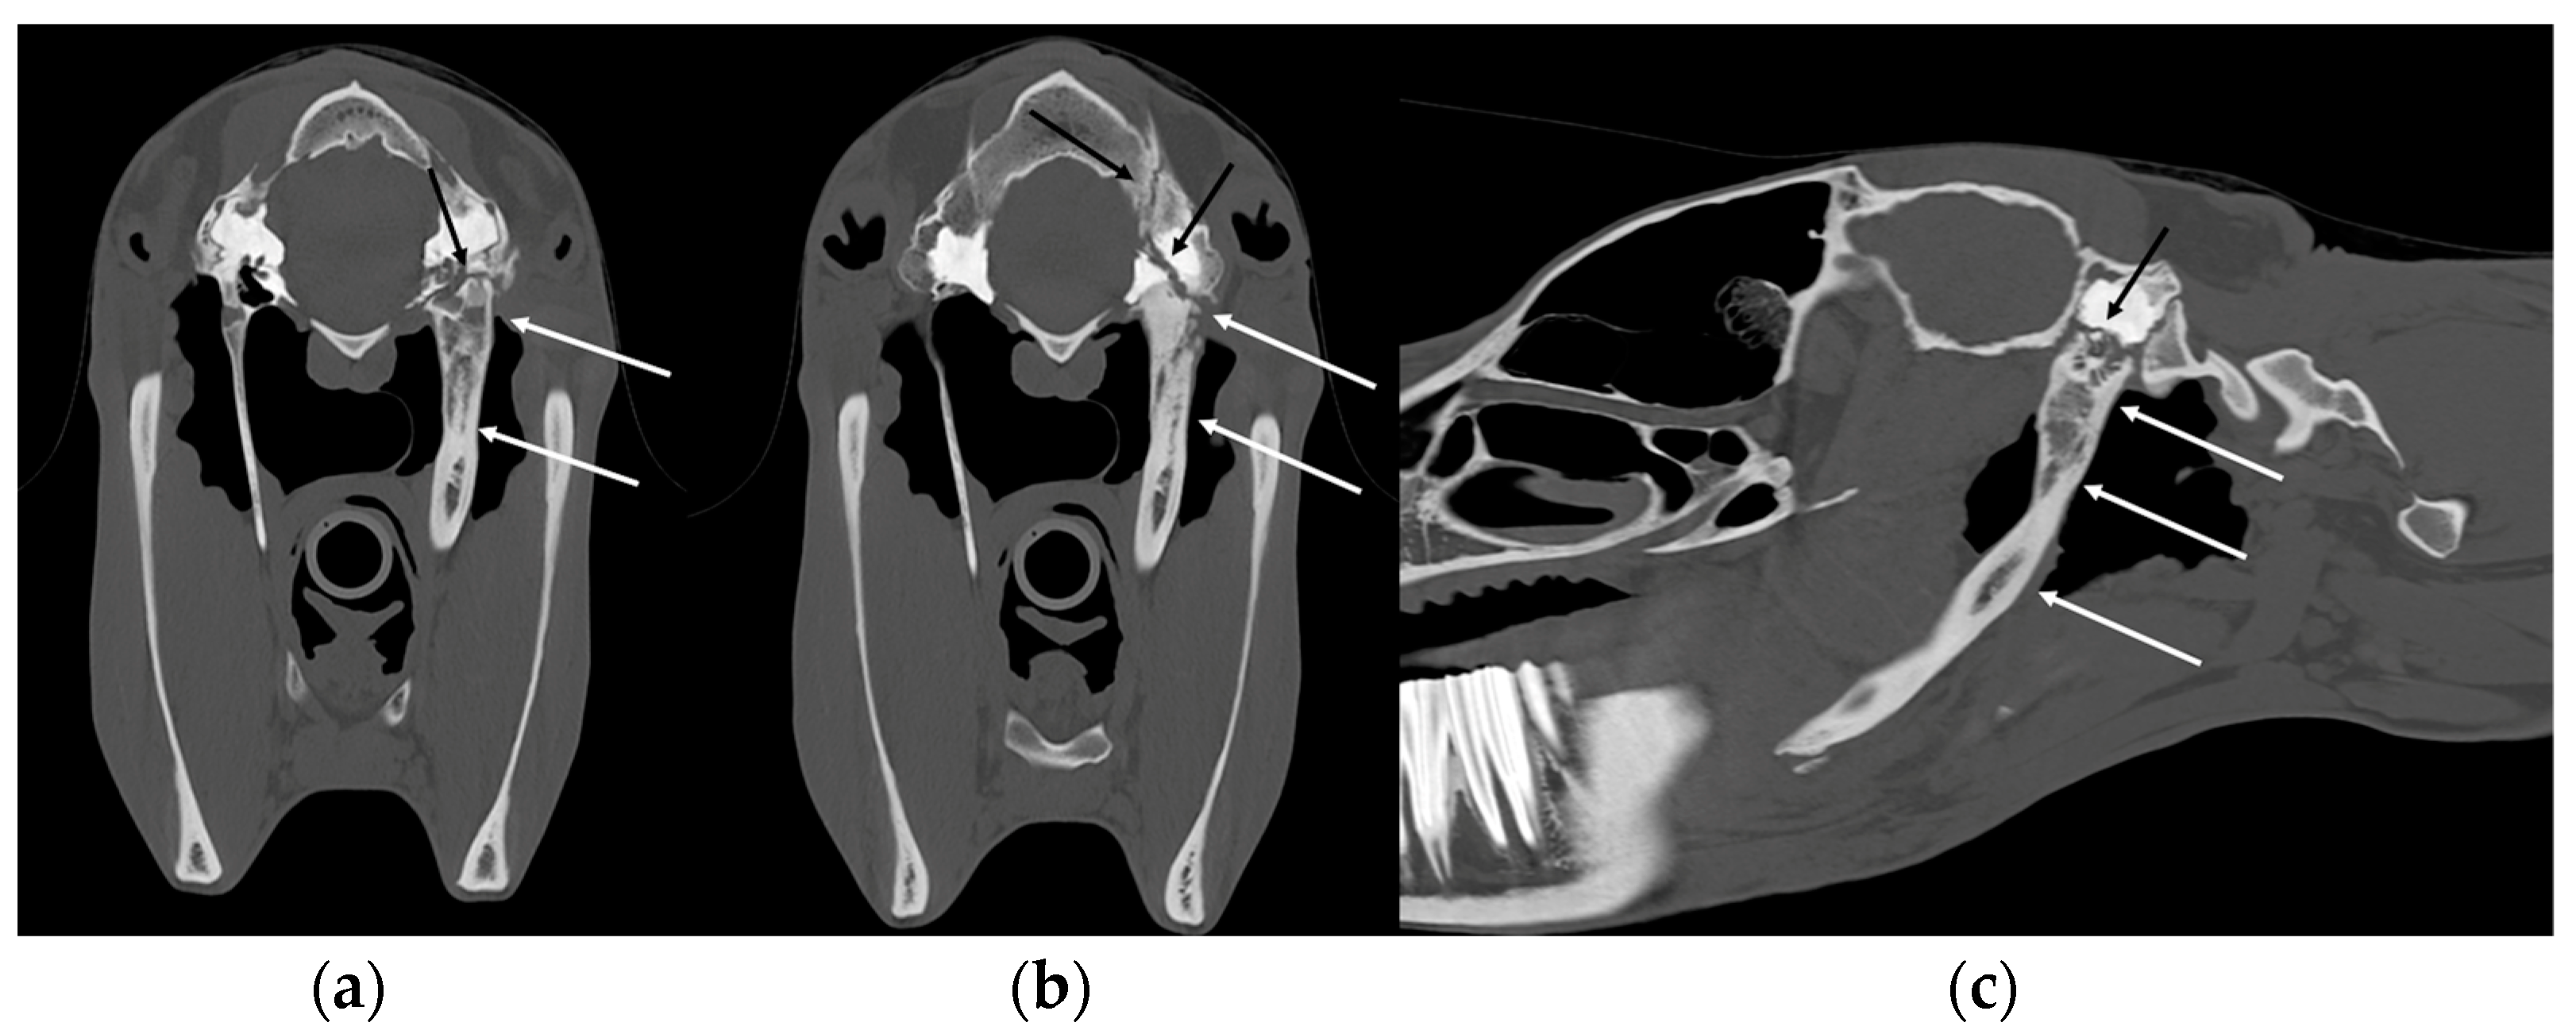

3.4. Temporohyoid Osteoarthropathy